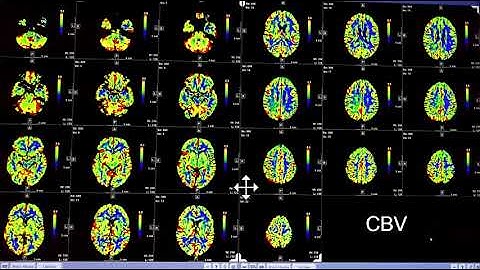

Video 3 of 3: How to Interpret a Brain CT Perfusion Scan for acute stroke